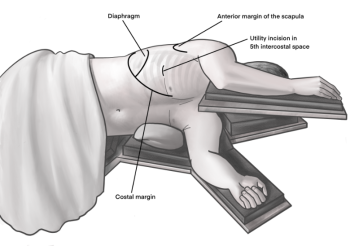

Inzision von etwa 4 cm Länge im Bereich der vorderen Axillarlinie am Oberrand der 5. Rippe um in den darüber liegenden 4. Interkostalraum zu gelangen. Als Orientierung ist hier oft eine gedachte Linie von der Schulterblattspitze zur Mamille hilfreich. Durchtrennen der Subkutis auf der Rippe mit dem Monopolarmesser. Anschließend schrittweise Präparation der Interkostalmuskulatur mit dem Monopolarmesser. Das Eröffnen der Pleura erfolgt stumpf digital. Austasten der Thoraxwand auf Verwachsungen und Einsetzen einer Wundschutzfolie.